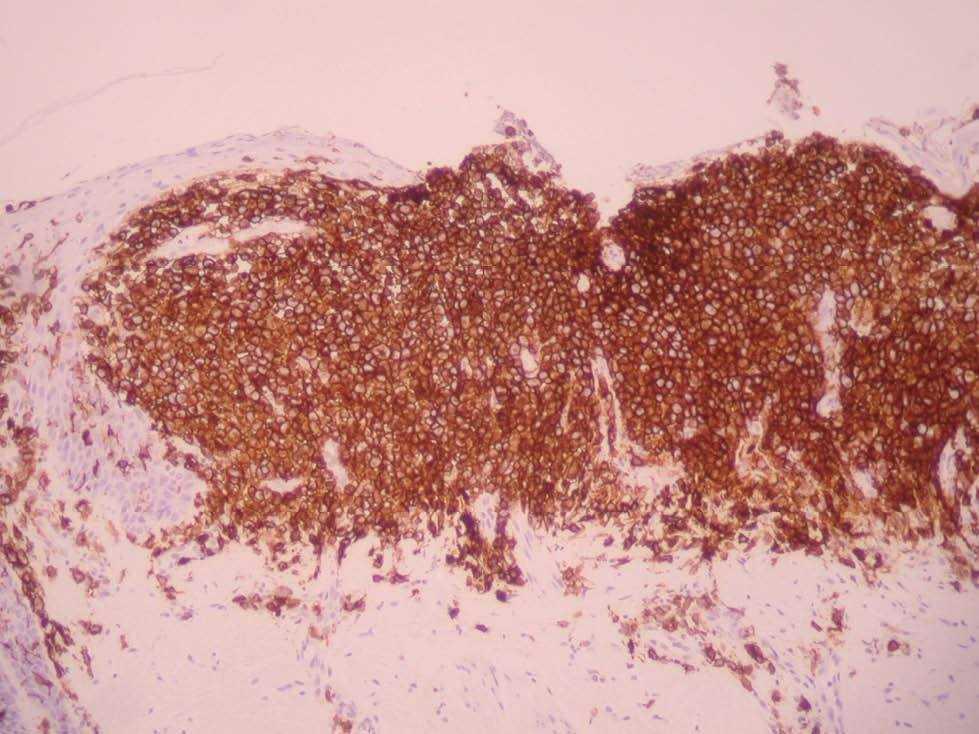

Una niña de 2 meses y medio de edad, sin antecedentes personales ni familiares de interés, fue remitida a nuestra consulta por la presencia desde el nacimiento de unas lesiones papulosas eritemato-amarillentas, de superficie costrosa en un número aproximado de 40 a 50, localizadas preferentemente en región cefálica, mitad superior del tronco, axilas e ingles. También se objetivó una pequeña úlcera en la región genital. La niña no tenía otra sintomatología sistémica acompañante. En la exploración se apreciaban múltiples pápulas eritemato-amarillentas, algunas con componente descamativo-costroso, localizadas en cuero cabelludo, mitad superior del tórax y espalda. En ambas ingles tenía placas úlcero-erosivas que se extendían hacia el periné (fig. 1) junto con pequeñas pápulas blanquecinas perianales. No se palpaban adenopatías, masas ni megalias. Una biopsia de una lesión de la espalda mostró un infiltrado epidermotropo que ocupaba y expandía la dermis papilar, que se acompañaba de ulceración y costra central (fig. 2). Dicho infiltrado estaba constituido fundamentalmente por células de núcleo arriñonado con amplios citoplasmas eosinófilos que con técnicas de inmunohistoquímica evidenciaron positividad para S-100 y CD1a (fig. 3). Salpicadas, se observaban células gigantes multinucleadas, y algún eosinófilo aislado.

Fig. 3.—Tinción positiva con CD1a.